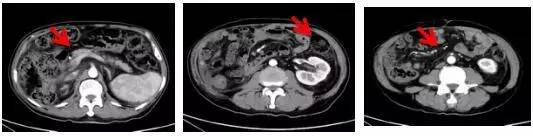

出现病情进展后给予患者更换靶向治疗药物后,患者治疗效果好,腹腔转移明显好转

2016.11.10

2017.3.13